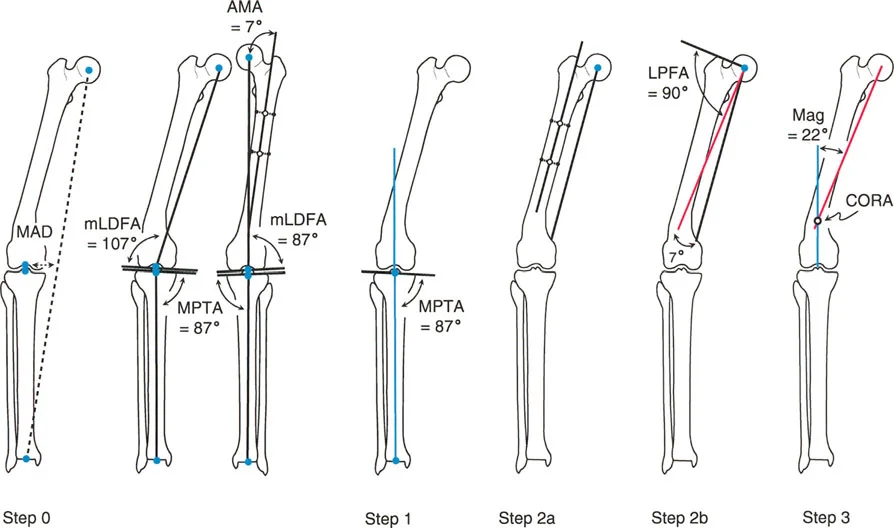

- أشعة الساق الكاملة الواقفة (Full-length Standing X-rays): هذه هي الأداة التشخيصية الأكثر أهمية لتشوهات الأطراف. يتم أخذ الصورة بينما يقف المريض، مما يسمح بتقييم المحور الميكانيكي للطرف بأكمله (من الورك إلى الكاحل) تحت تأثير تحمل الوزن. تتيح هذه الصور للجراح قياس زوايا محددة بدقة وتحديد "مركز دوران التشوه" (CORA) – وهو النقطة المحورية التي يجب أن يتم التصحيح حولها.

إن نجاح جراحة تصحيح تشوهات الأطراف يعتمد بشكل كبير على التخطيط المسبق الدقيق. هذا التخطيط أشبه برسم خارطة طريق هندسية تضمن أن كل خطوة جراحية تقود إلى النتيجة المرجوة. يعتمد هذا التخطيط على "مبادئ بالي" التي تحدد ثلاثة متغيرات هندسية أساسية في كل حالة:

- مركز دوران التشوه (CORA - Center of Rotation of Angulation): هذه هي النقطة المحورية للتشوه في العظم. يحددها الجراح من خلال رسم محاور الطرف قبل الجراحة.

- محور تصحيح الزاوية (ACA - Angulation Correction Axis): هذه هي النقطة التي يدور حولها الجزء البعيد من العظم لتصحيح التشوه. يتحكم الجراح في هذه النقطة عن طريق وضع المفصلات على المثبت الخارجي أو نقطة الارتكاز للوحة التثبيت.

- مستوى قطع العظم (Osteotomy Level): هذا هو الموقع الفعلي الذي يتم فيه قطع العظم. يتحكم الجراح بشكل كامل في هذا المتغير، ويتم اختياره بناءً على عوامل مثل الأنسجة الرخوة، وجودة العظم، ونوع الأجهزة المستخدمة.

النتيجة النهائية للتصحيح تعتمد كليًا على كيفية ارتباط هذه المتغيرات الثلاثة ببعضها البعض. الفشل في التخطيط الدقيق يمكن أن يؤدي إلى "تشوهات ثانوية" غير مرغوب فيها، مثل انحراف المحور الميكانيكي أو ترجمة (إزاحة) العظم.